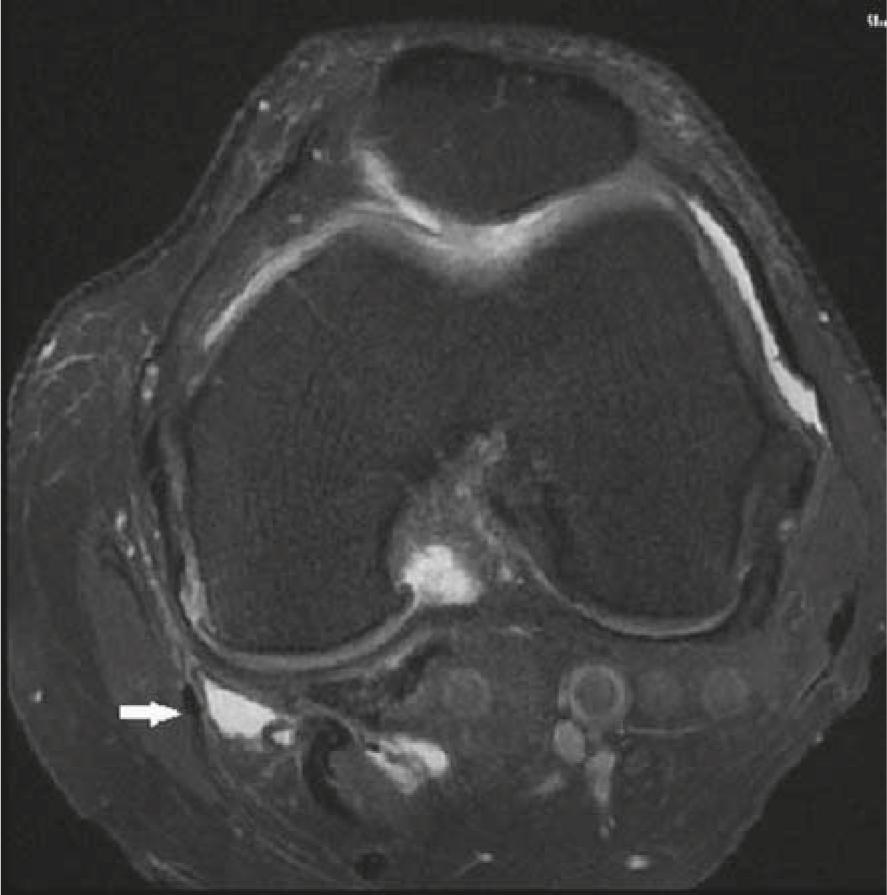

Inflammation occurring in the PA, SM-TCL (Figure 4) and MCL bursa in the medial of knee is an important cause of pain. Obesity, degenerative joint disease, valgus deformity, trauma, impaired joint stability, excessive loading on the joint and sporting activity are important causes of inflammation in the bursae.15 Some authors have suggested that the structure of the female pelvis creates a predisposition to bursitis.16 We determined no relation between gender and the prevalence of bursitis (p = 0.954). Toktas et al. investigated the prevalence of pes anserine bursitis in patients with OA.17 They determined a greater pes anserine thickness not only in OA patients with bursitis, but also in OA patients without bursitis compared to the control group. We selected all our cases from OA patients and took the OA grade (mild and severe) as our reference points. We also investigated the presence of SM-TCL and MCL bursitis in addition to PA bursitis. We observed higher prevalence of medial periarticular bursitis in patients with severe OA compared to those with mild OA (p = 0.023). Our results are compatible with recent studies revealing as association between OA and pes anserine bursitis.16

The axial fat saturated proton density weighted image demonstrates a fluid collection in the SM-TCL bursa.